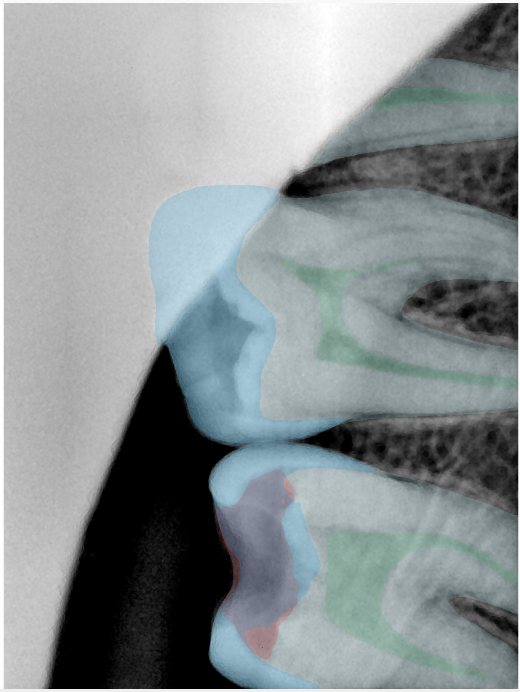

CR/DR 牙齿分割阶段记录

当前进展

- 完成了 CR/DR 牙齿相关分割训练

- 当前结果已经达到阶段预期,但仍有细节问题需要继续处理

相关测试

遇到的问题

- 训练过程中出现过 mask 下移问题

- 部分结果会出现 box 填充异常

- mask 边缘仍然有比较明显的锯齿感

参考

第三版算法分辨率效果比较

Updated: 2026-04-13(更新日期)

| 编号 | 原图 | 第一版 | 第二版 | 第三版 1216x1600 | 第三版 768x1024 | 第三版 1120x1120 |